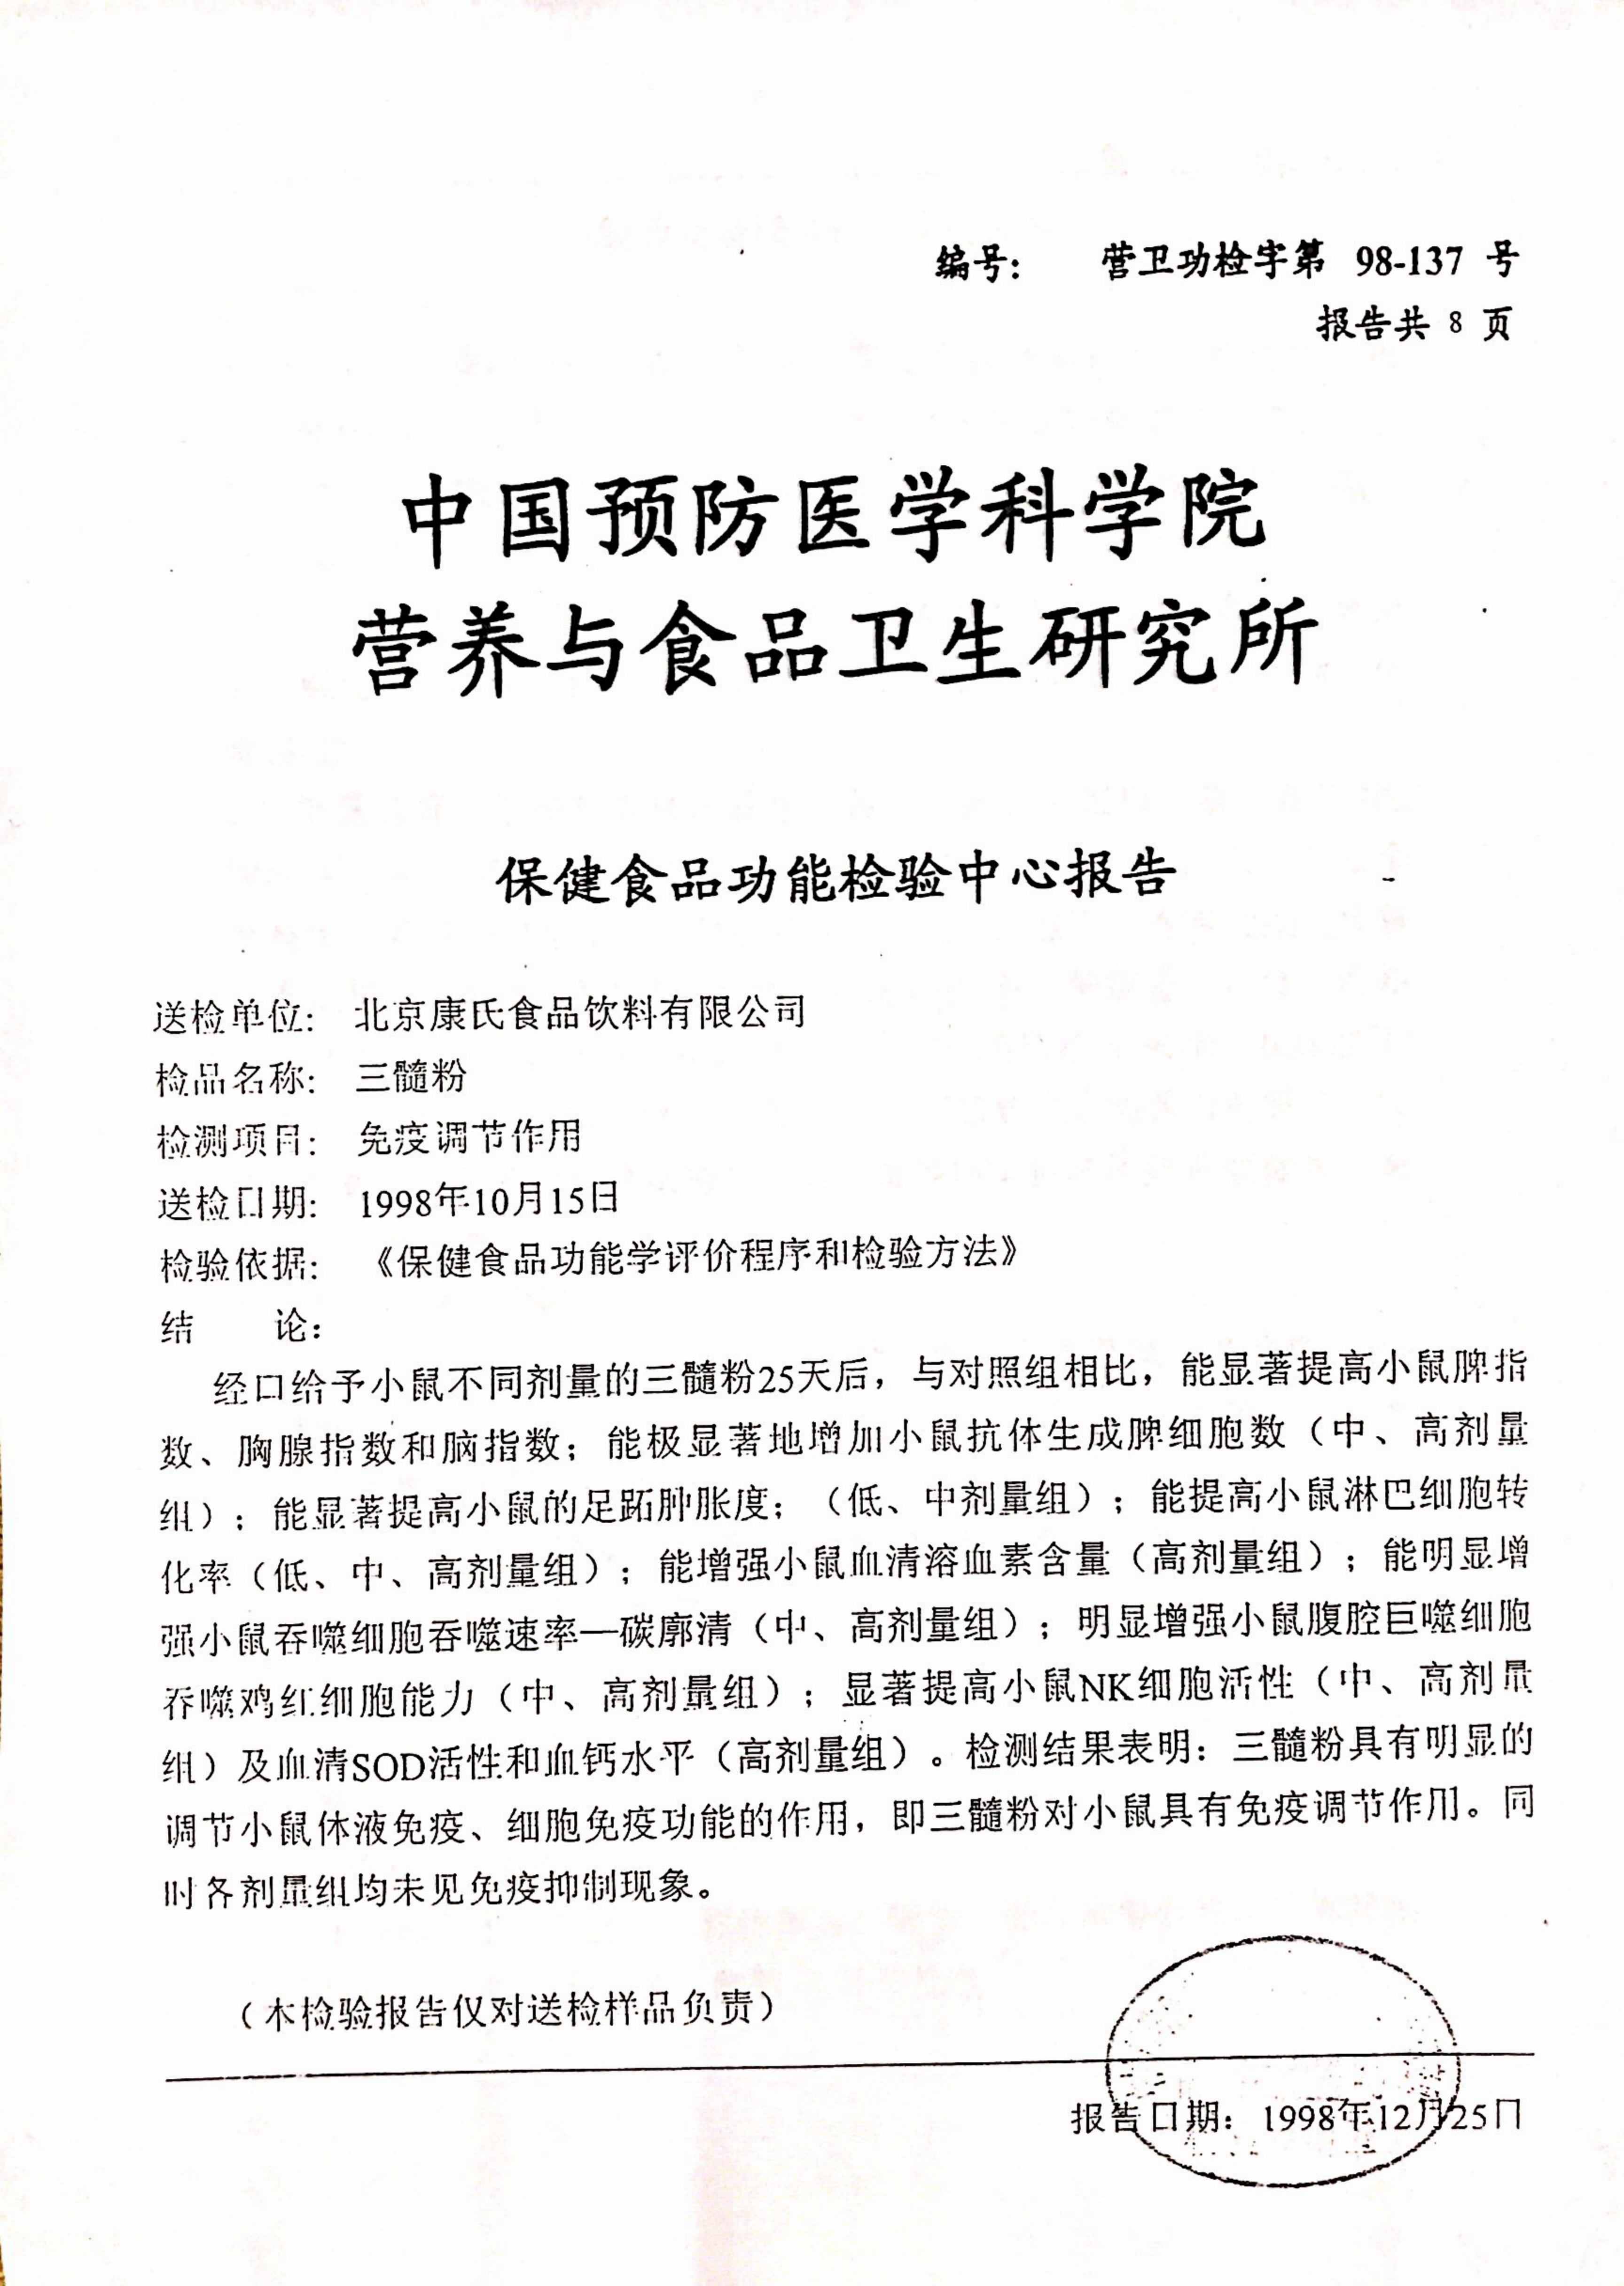

七项免疫功能检验报告

诺普乐公司将髓养生智慧与现代免疫学研究成果深度融合,开发专注于机体防御力提升的营养解决方案。以髓质精华为核心,精准配比多种免疫营养素,从细胞层面筑牢健康防线,帮助机体维持良好的免疫稳态,从容应对内外环境挑战。

“三髓粉”对绝经后妇女骨密度及骨症状改善的研究

服用三髓粉1〜5年对老年人骨密度、临床症状及骨折的影响